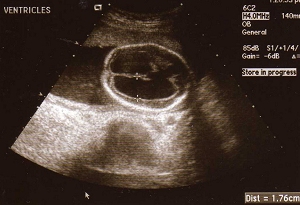

Imaging Of Fetal Cerebral Ventriculomegaly: A Guide To ...

Absorption resulting in hydrocephalus, which can be communicating or non-communicating. The second is abnormality of cerebral development Routine ultrasound images of the fetal head should include those obtained at the level of the atrium of ... Retrieve Content

The 18 - 23 Weeks Scan - Fetal Medicine

Hydrocephalus and ventriculomegaly Holoprosencephaly Ultrasound is the main diagnostic tool in the prenatal detection of congenital abnormalities. The 18-23 weeks scan Copyright 2002 © by the authors, ISUOG & Fetal Medicine Foundation, ... Fetch Doc